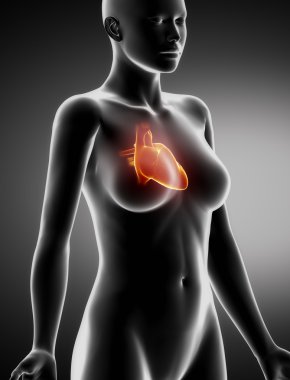

Kalbin anatomik incelemesi. Kalp sorunları, kalp krizi. Ameliyat mı? 3D görüntüleme. Siluet. Kalp, dolaşım sisteminin kan damarlarına kan pompalayan kaslı bir organdır.

Kırmızıİzole edilmişİnsanSağlıkBaşıİlaçSağlık hizmetlerierkekTıbbidikkatAdamsiyahYapıKardiyolojikalpHastagövdeKarnıEğitimİçeridebiyolojiBilimSistemGöğüsSaldırın!AcıorgvenKasÇizelgeİskeletanatomiKas gücübeyindiyagramBilim kurgux ışınısindirimAğrıKardiyakiskeletanatomikkoronerkalp krizi3d oluşturmakaslı organBenzer İçerikler